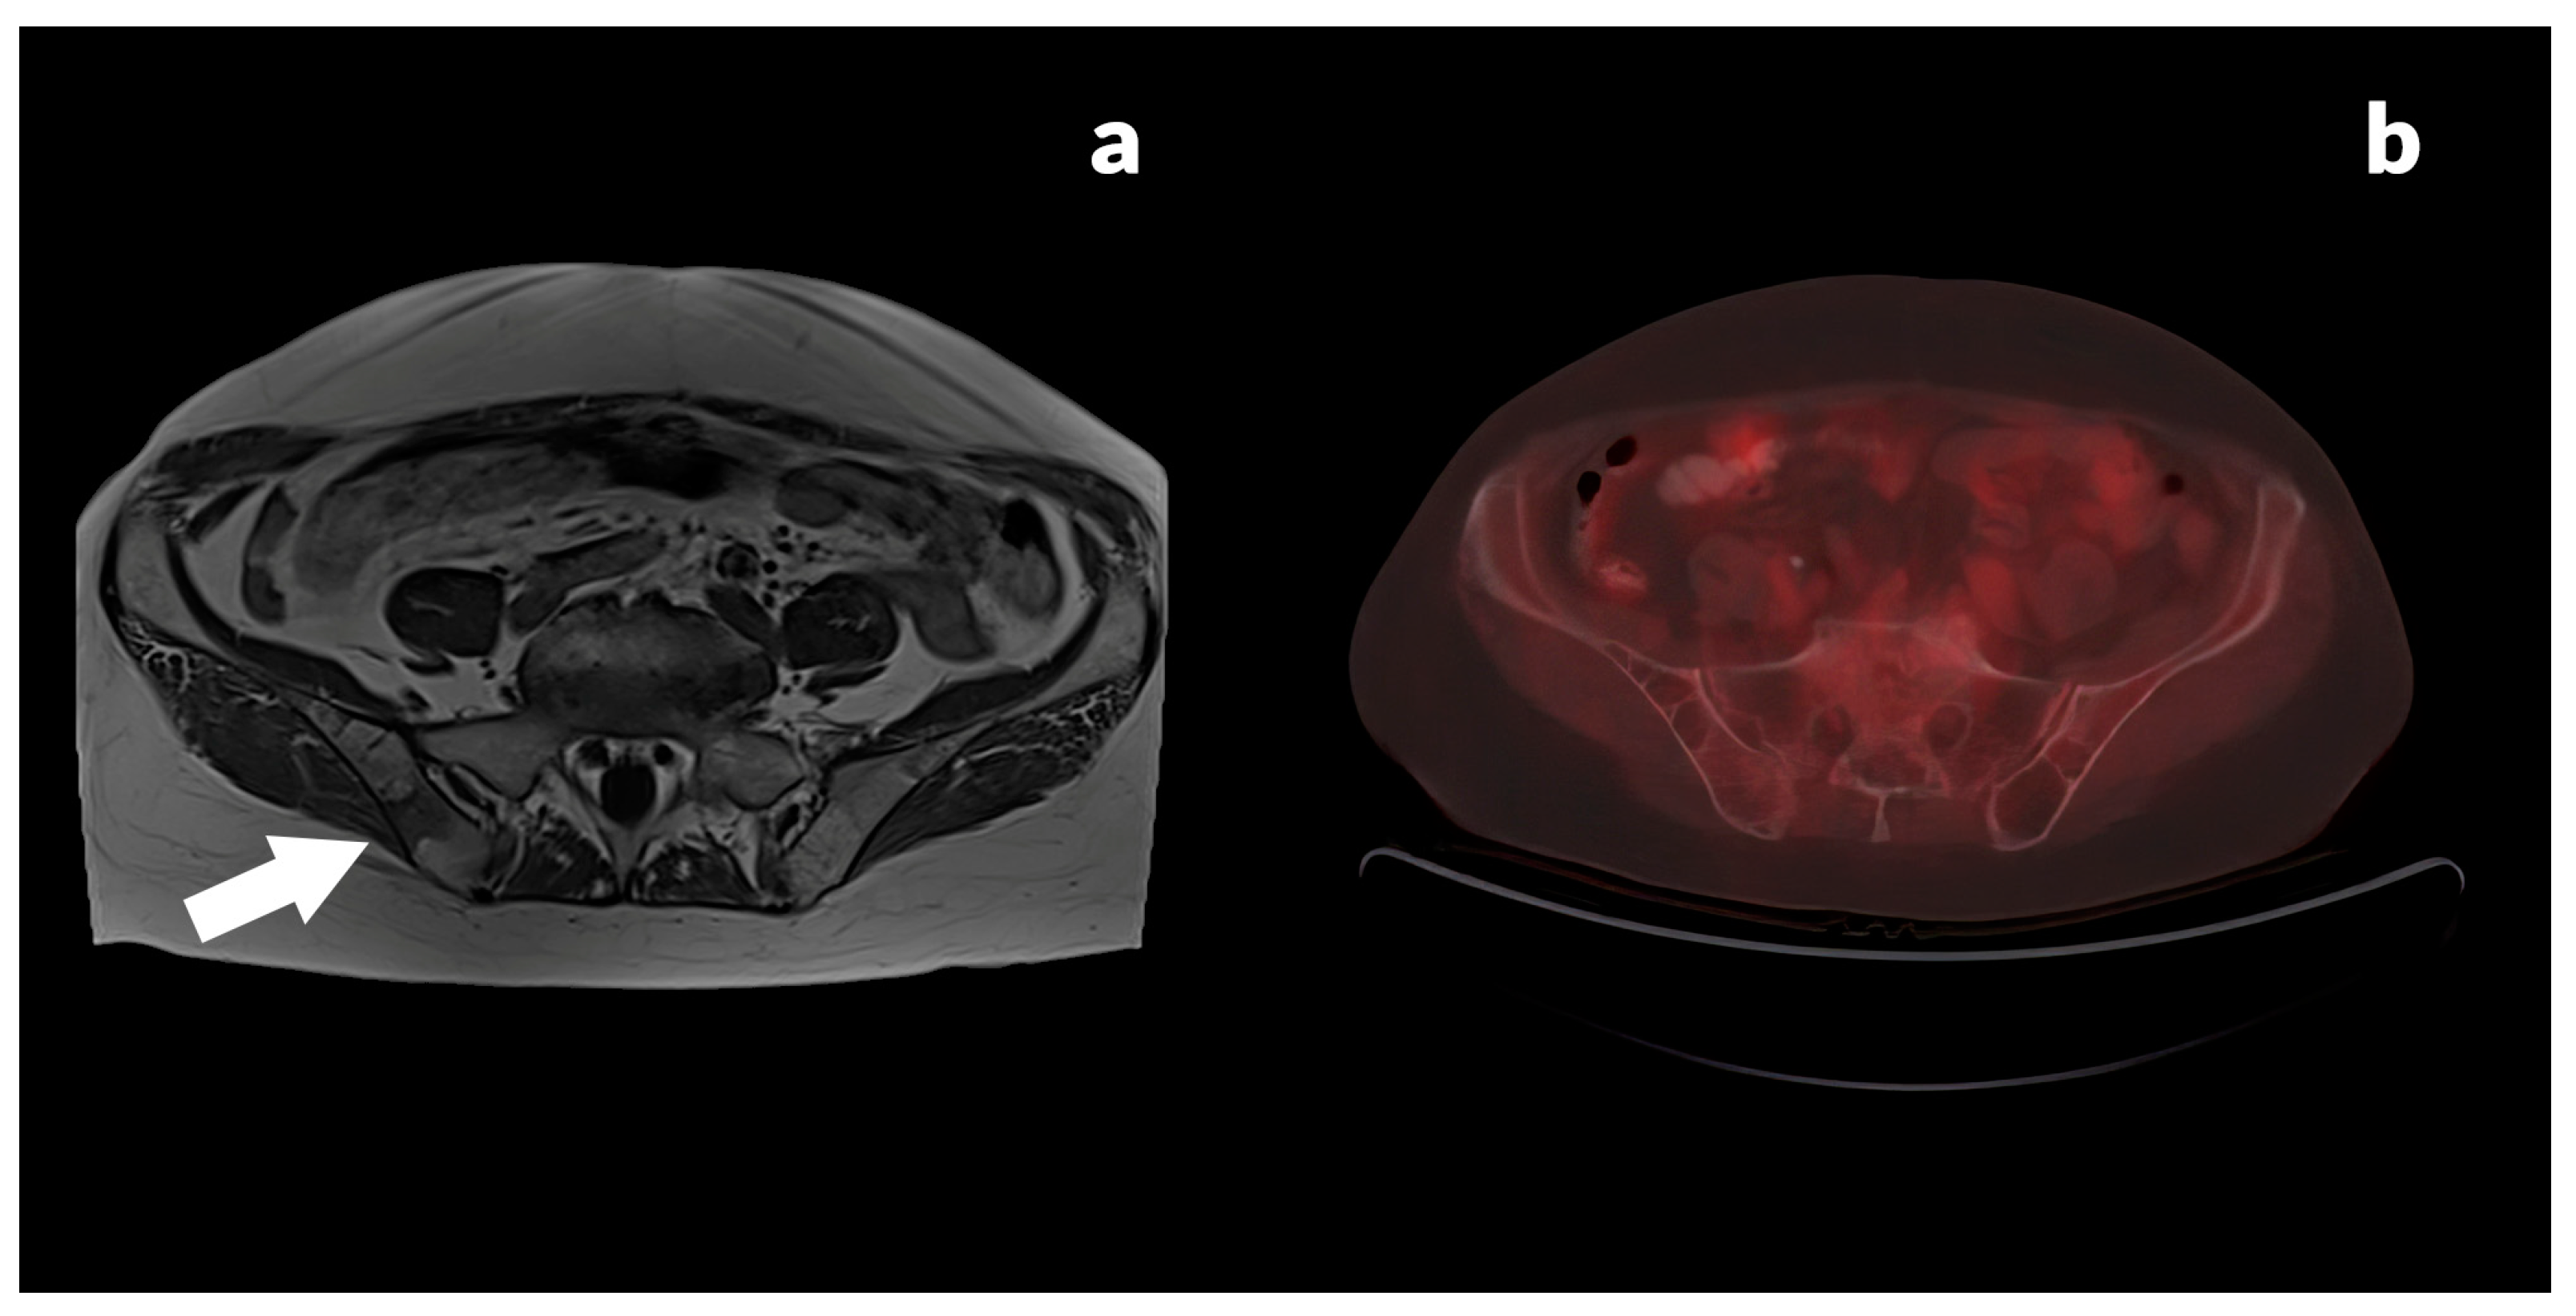

3.2.3. Case Reports